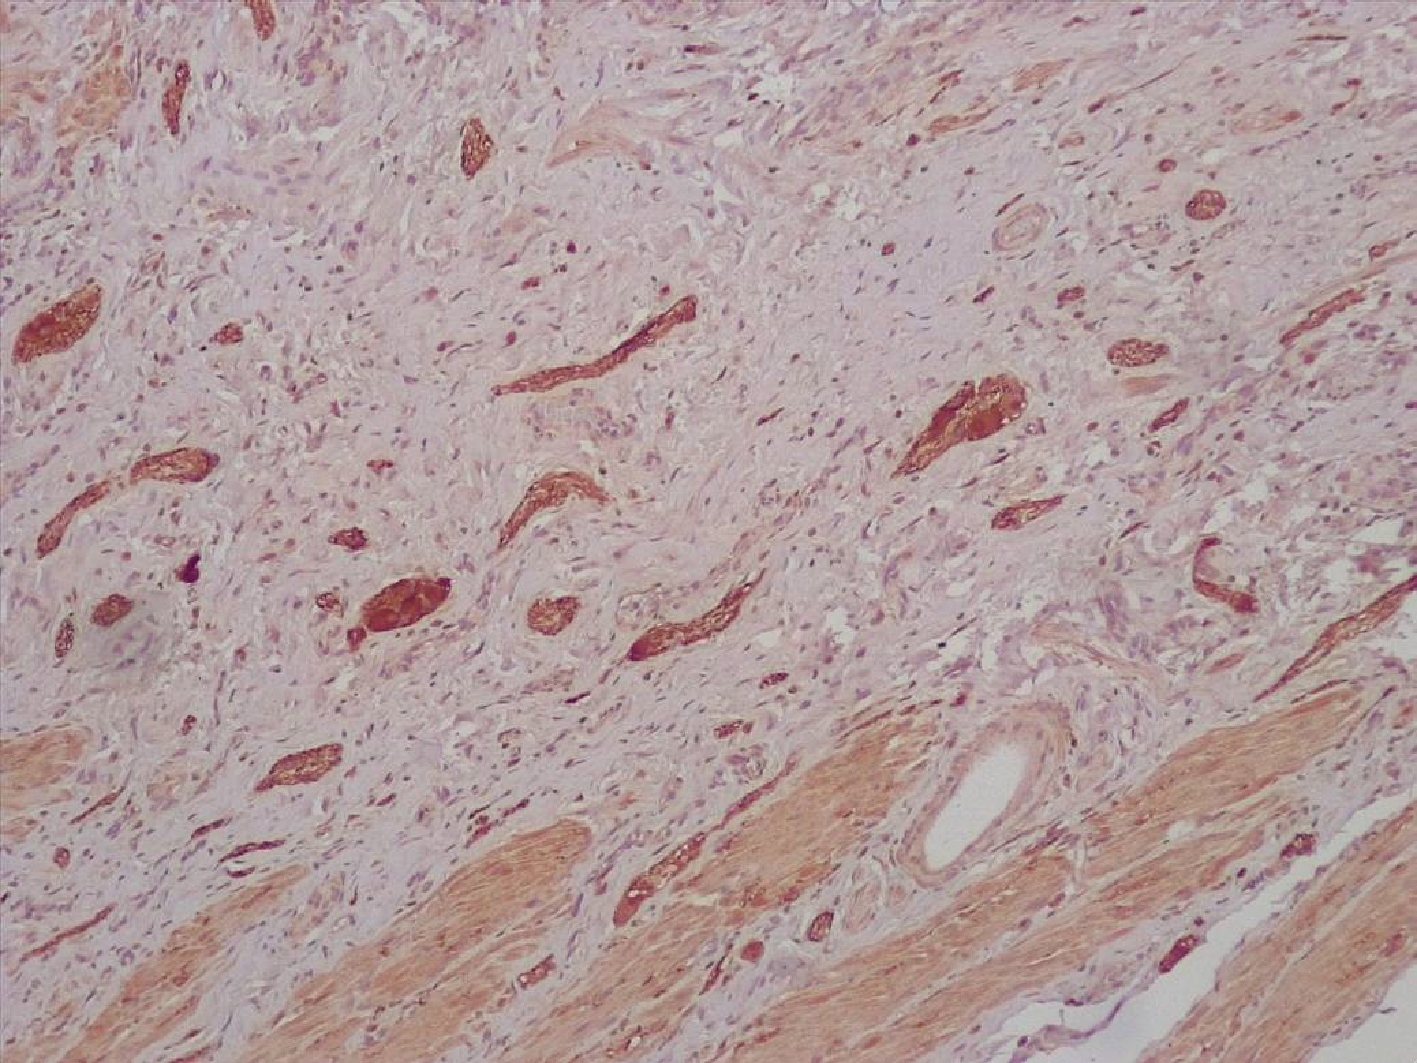

Для уточнения нейроэндокринного профайла карциномы были использованы антитела к хромогранину А и синаптофизину, которые выявили наличие нейроэндокринных гранул в цитоплазме части опухолевых клеток (рис.2).

Рис.2. Яркая экспрессия нейрон-специфической энолазы в цитоплазме опухолевых клеток тубулярной аденокарциномы. Иммуногистохимическое исследование с антителами к синаптофизину. Увеличение Х200.